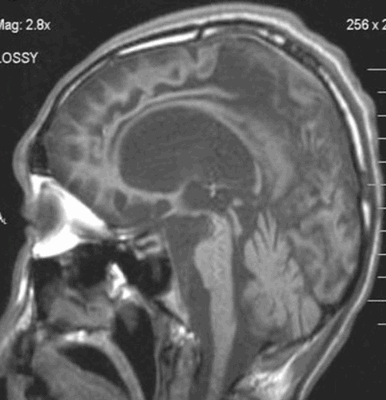

- МРТ головного мозга. В начальной стадии может соответствовать норме. В дальнейшем обнаруживаются атрофические изменения головного мозга, наиболее выраженные в мозжечке и подкорковых ганглиях. МРТ позволяет исключить рассеянный склероз, энцефалит, опухолевые процессы.

Атрофия головного мозга на МРТ

Магнитно-резонансная томография признана одним из наиболее информативных нейровизуализационных методов исследования. В ходе процедуры получают детальные послойные снимки головного мозга, позволяющие оценить соответствие органа нормам.

МРТ актуальна при диагностике посттравматических состояний, воспалительных, опухолевых, нейродегенеративных изменений. Одно из самых тяжелых нарушений, выявляемых с помощью томографии — атрофия головного мозга. Это хроническое прогрессирующее заболевание, сопровождающееся гибелью нейронов, уменьшением объема и плотности структур головного мозга.

Как выглядит атрофия головного мозга на МРТ?

Диффузная атрофия головного мозга с вентрикуломегалией

Явление дифференцируют с истинной гидроцефалией. Главный МРТ-признак атрофии головного мозга — пропорциональное расширение внутренних и наружных ликворных церебральных пространств, что указывает на уменьшение объема структур органа. Выраженность изменений оценивают с помощью церебро-вентрикулярного индекса (ЦВИ Эванса). Учитывают и другие отклонения в ткани головного мозга.

Симптомы патологии на МРТ-снимках:

увеличение ЦВИ Эванса;

расширение субарахноидальных борозд и щелей;

снижение плотности мозговой ткани;

дистрофия белого вещества;

уменьшение долей мозга в размерах.